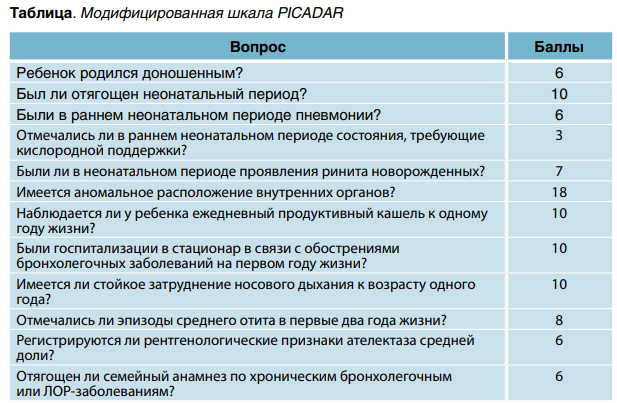

Характерная клинико-анамнестическая картина с ранней манифестацией заболевания, тотальным поражением органов дыхания и аномалиями расположения внутренних органов позволяет заподозрить ПЦД и провести целенаправленное обследование для уточнения диагноза. В помощь практикующему педиатру разработана предиктивная шкала для выявления симптомов ПЦД — PICADAR (PrImary CiliAry DyskinesaA Rule). Ниже приводим модифицированную нами шкалу PICADAR, адаптированную к условиям России. При сумме баллов ≥ 75 вероятность ПЦД составляет 90,25 %, при ≥ 80 — ≥ 95 %. Чувствительность и специфичность шкалы равняются 96,25 % и 97,5 % соответственно. В таблице представлены вопросы о здоровье ребенка и соответствующие ответу баллы. В качестве скрининг-диагностики для выявления ПЦД используют определение назального уровня оксида азота (NO). При ПЦД он заметно снижен, что позволяет заподозрить заболевание и применить специфические методы диагностики (оценка подвижности цилиарного эпителия путем световой микроскопии и его электронная микроскопия).